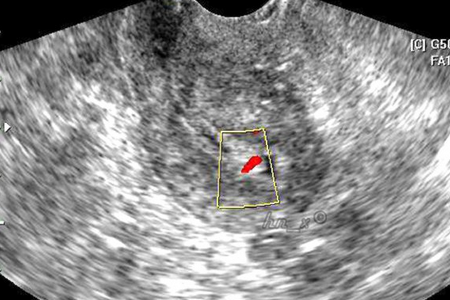

产后一些妈妈感觉到腹部有下坠和疼痛等症,去医院检查后发现是有盆腔积液。那么,产后盆腔积液是怎么引起的呢?

产妇分娩后,体内激素下降或者在产后42天时处于排卵期等,就会导致少量的盆腔积液出现,这种为正常的生理现象,妈妈们不用担心,它会随着产妇内分泌的恢复或者月经结束,积液会自行吸收。

女性在生产后,身体虚弱,免疫能力低下,宫颈口处于扩张状态,此时,若不注意生殖部位的清洁卫生或过早进行性生活等,均可引发细菌滋生而导致盆腔感染发炎,出现盆腔积液。

如果产后子宫内有残留物,如胎盘、胎膜残留等,也会造成持续阴道出血以及感染产后盆腔炎,出现盆腔积液的情况。

如果妈妈在产后急于瘦身,不当使用束腹带,会导致盆腔血流不畅,再加上饮食过少,营养不足,抵抗力下降,所以容易诱发盆腔炎,进而出现盆腔积液。